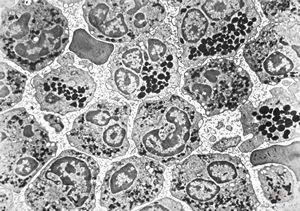

M,62y. | bone marrow - plasmocytoma

M,64y. | bone marrow - plasmocytoma

bone marrow … plasmocytoma (parafin-embedded sample)